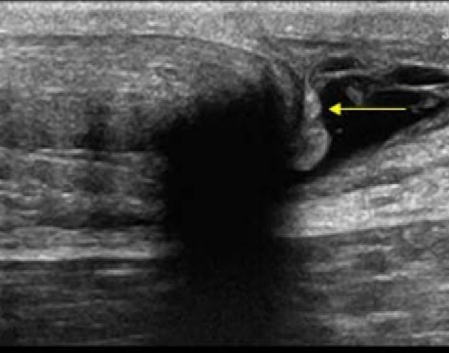

Identify this image.

Achilles tendon tear